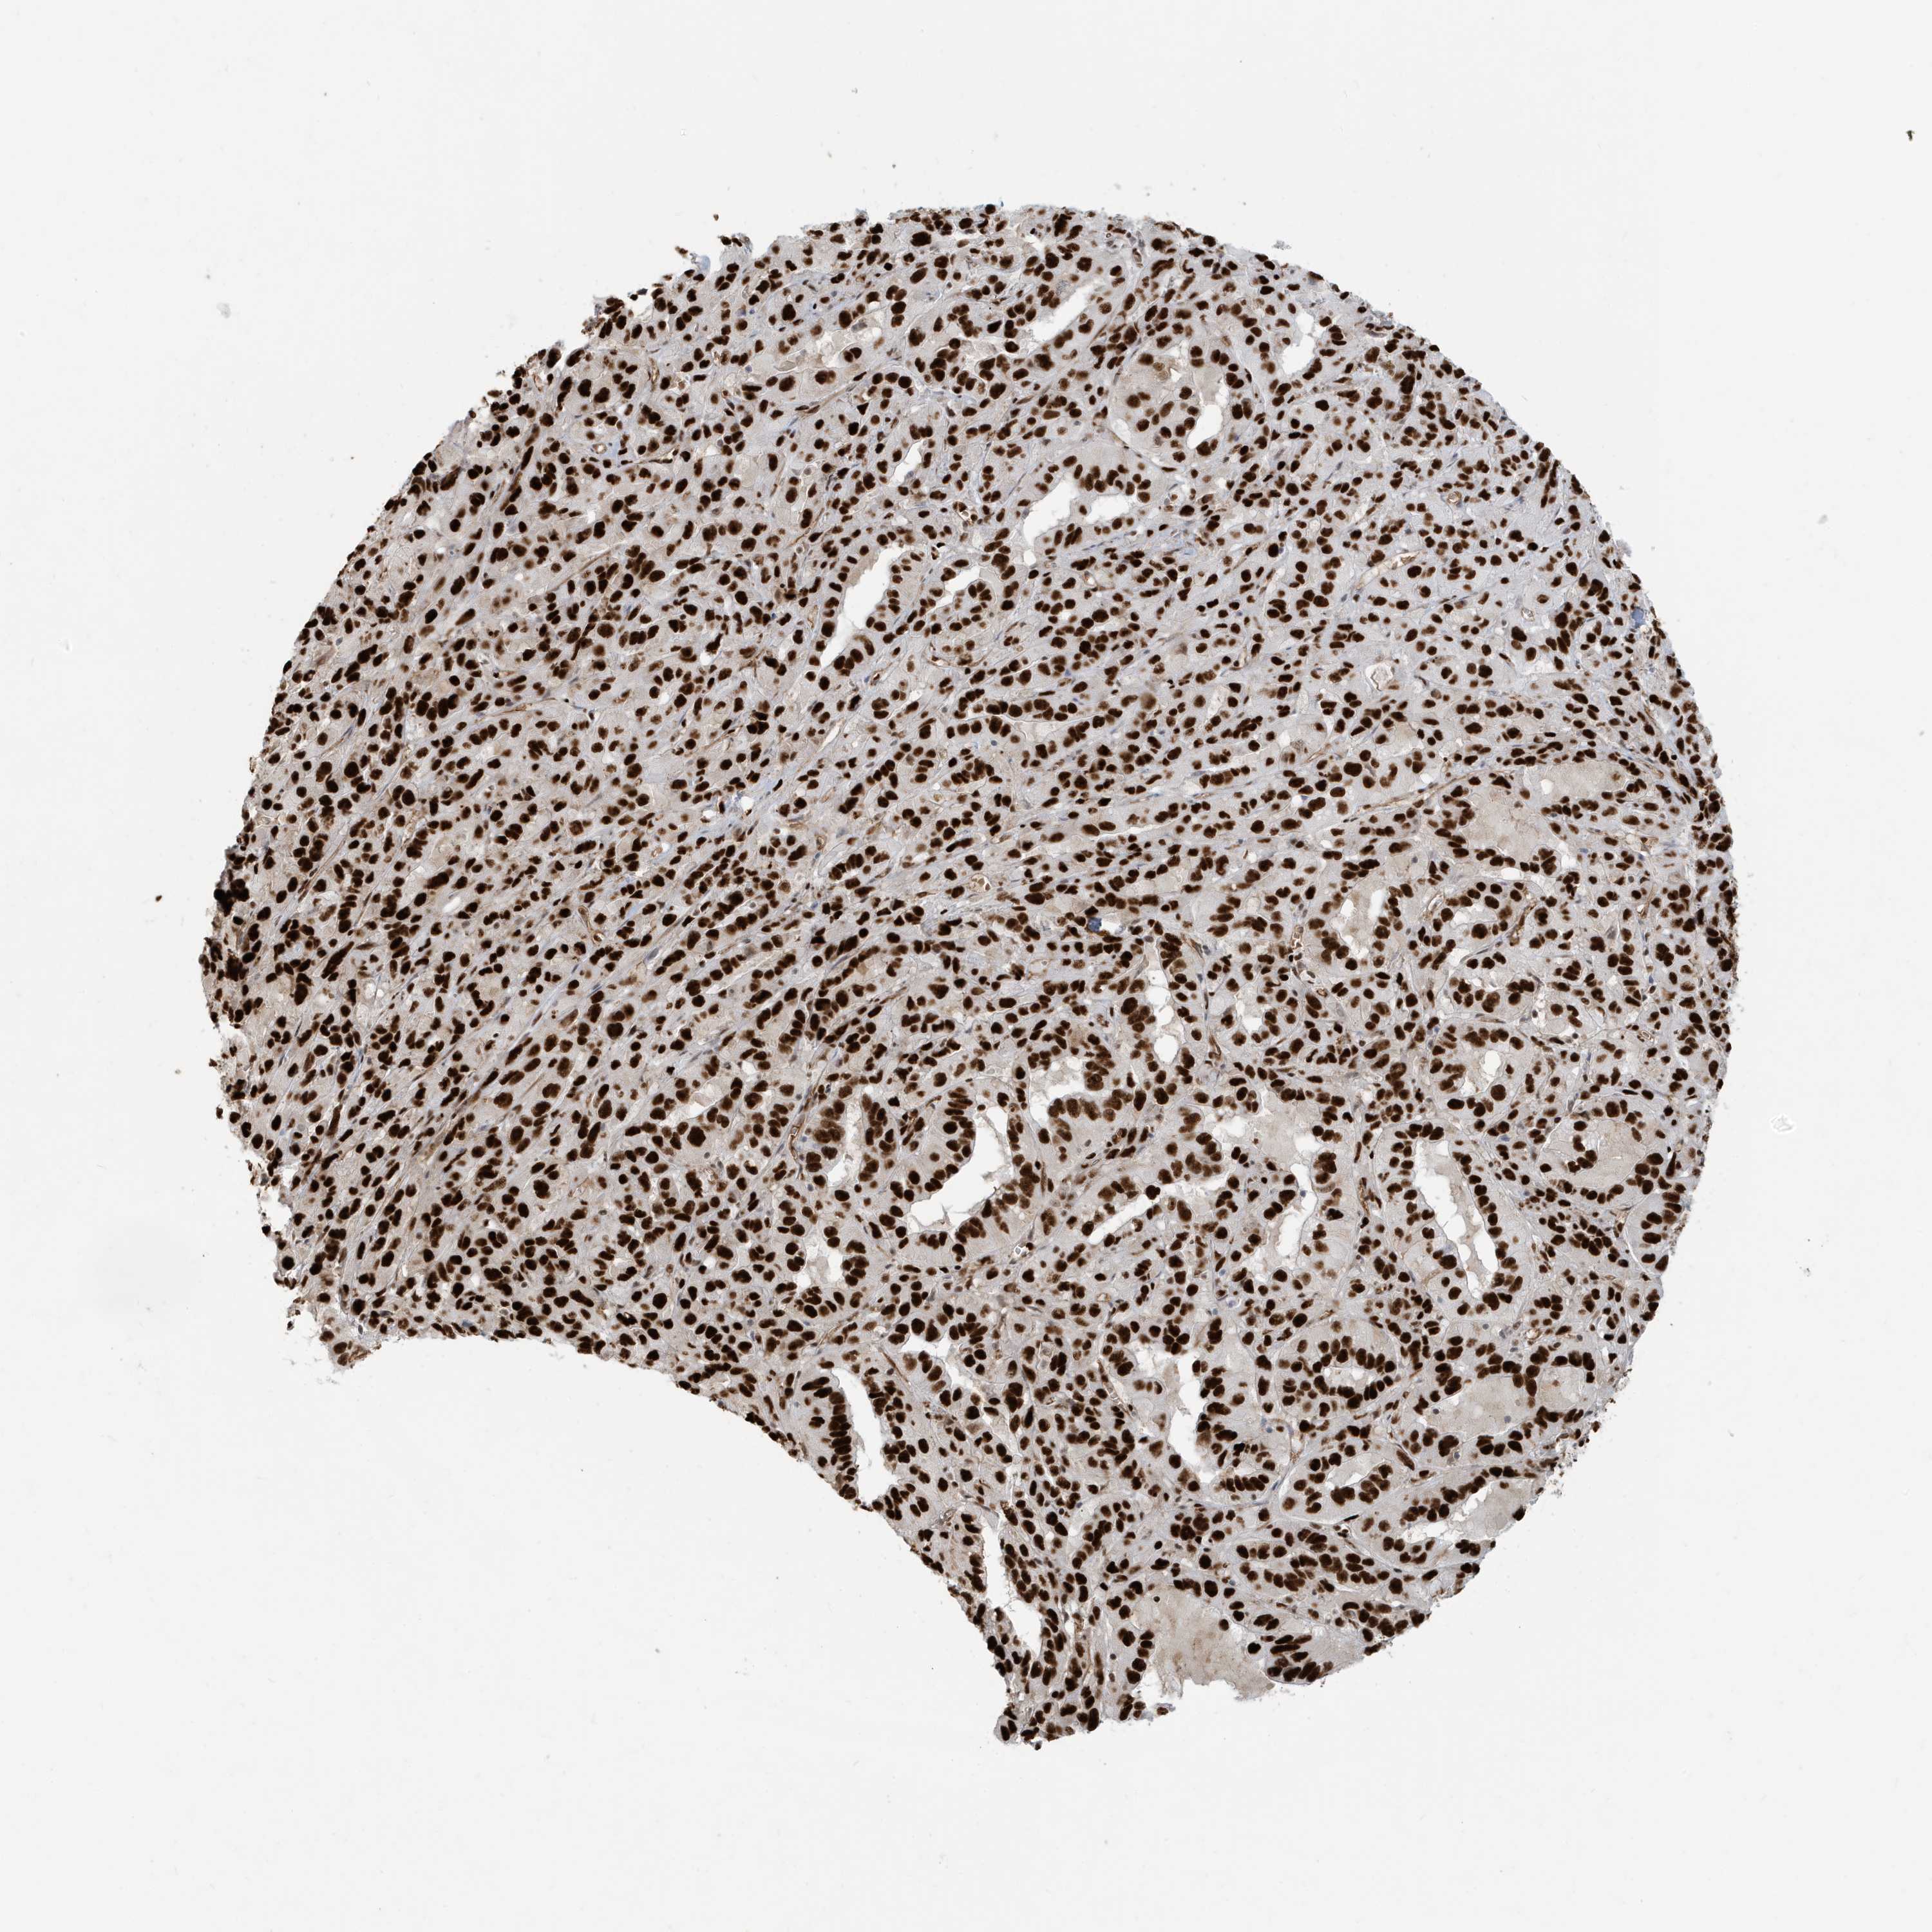

PANCREATIC CANCER - Protein expressioni

A mouse-over function shows sample information and annotation data. Click on an image to view it in a full screen mode. Samples can be filtered based on level of antibody staining by selecting one or several of the following categories: high, medium, low and not detected. The assay and annotation is described here.

Note that samples used for immunohistochemistry by the Human Protein Atlas do not correspond to samples in the TCGA dataset.

Antibody stainingi

Antibody staining in the annotated cell types in the current human tissue is reported as not detected, low, medium, or high, based on conventional immunohistochemistry profiling in selected tissues. This score is based on the combination of the staining intensity and fraction of stained cells.

Each image is clickable and will lead to virtual microscopy that enables deeper exploration of all samples and also displays staining intensity scores, fraction scores and subcellular localization as well as patient and tissue information for each sample.

Antibody HPA030762

Staining

High

Medium

Low

Not detected

Intensity

Strong

Moderate

Weak

Negative

Quantity

>75%

75%-25%

<25%

None

Location

Nuclear

Cytoplasmic/membranous

Cytoplasmic/membranous,nuclear

Adenocarcinoma, NOS